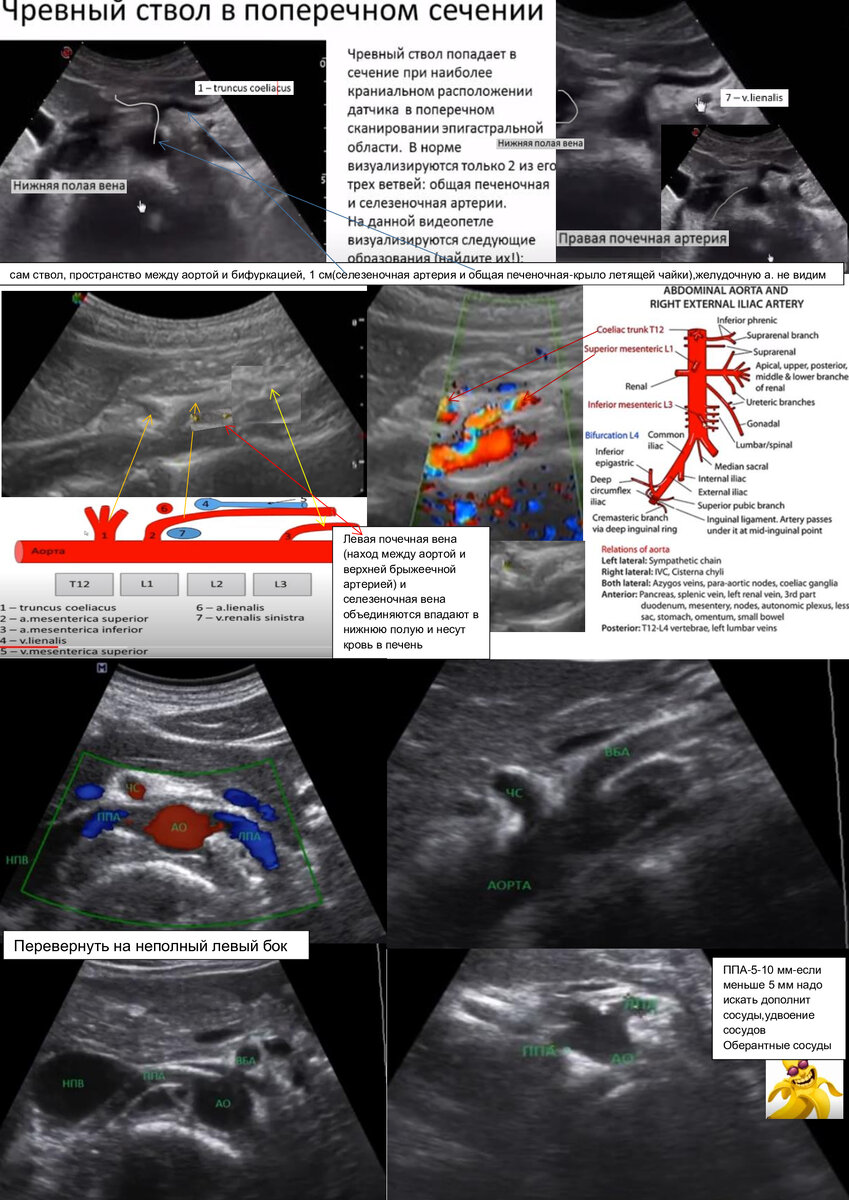

Сосуды